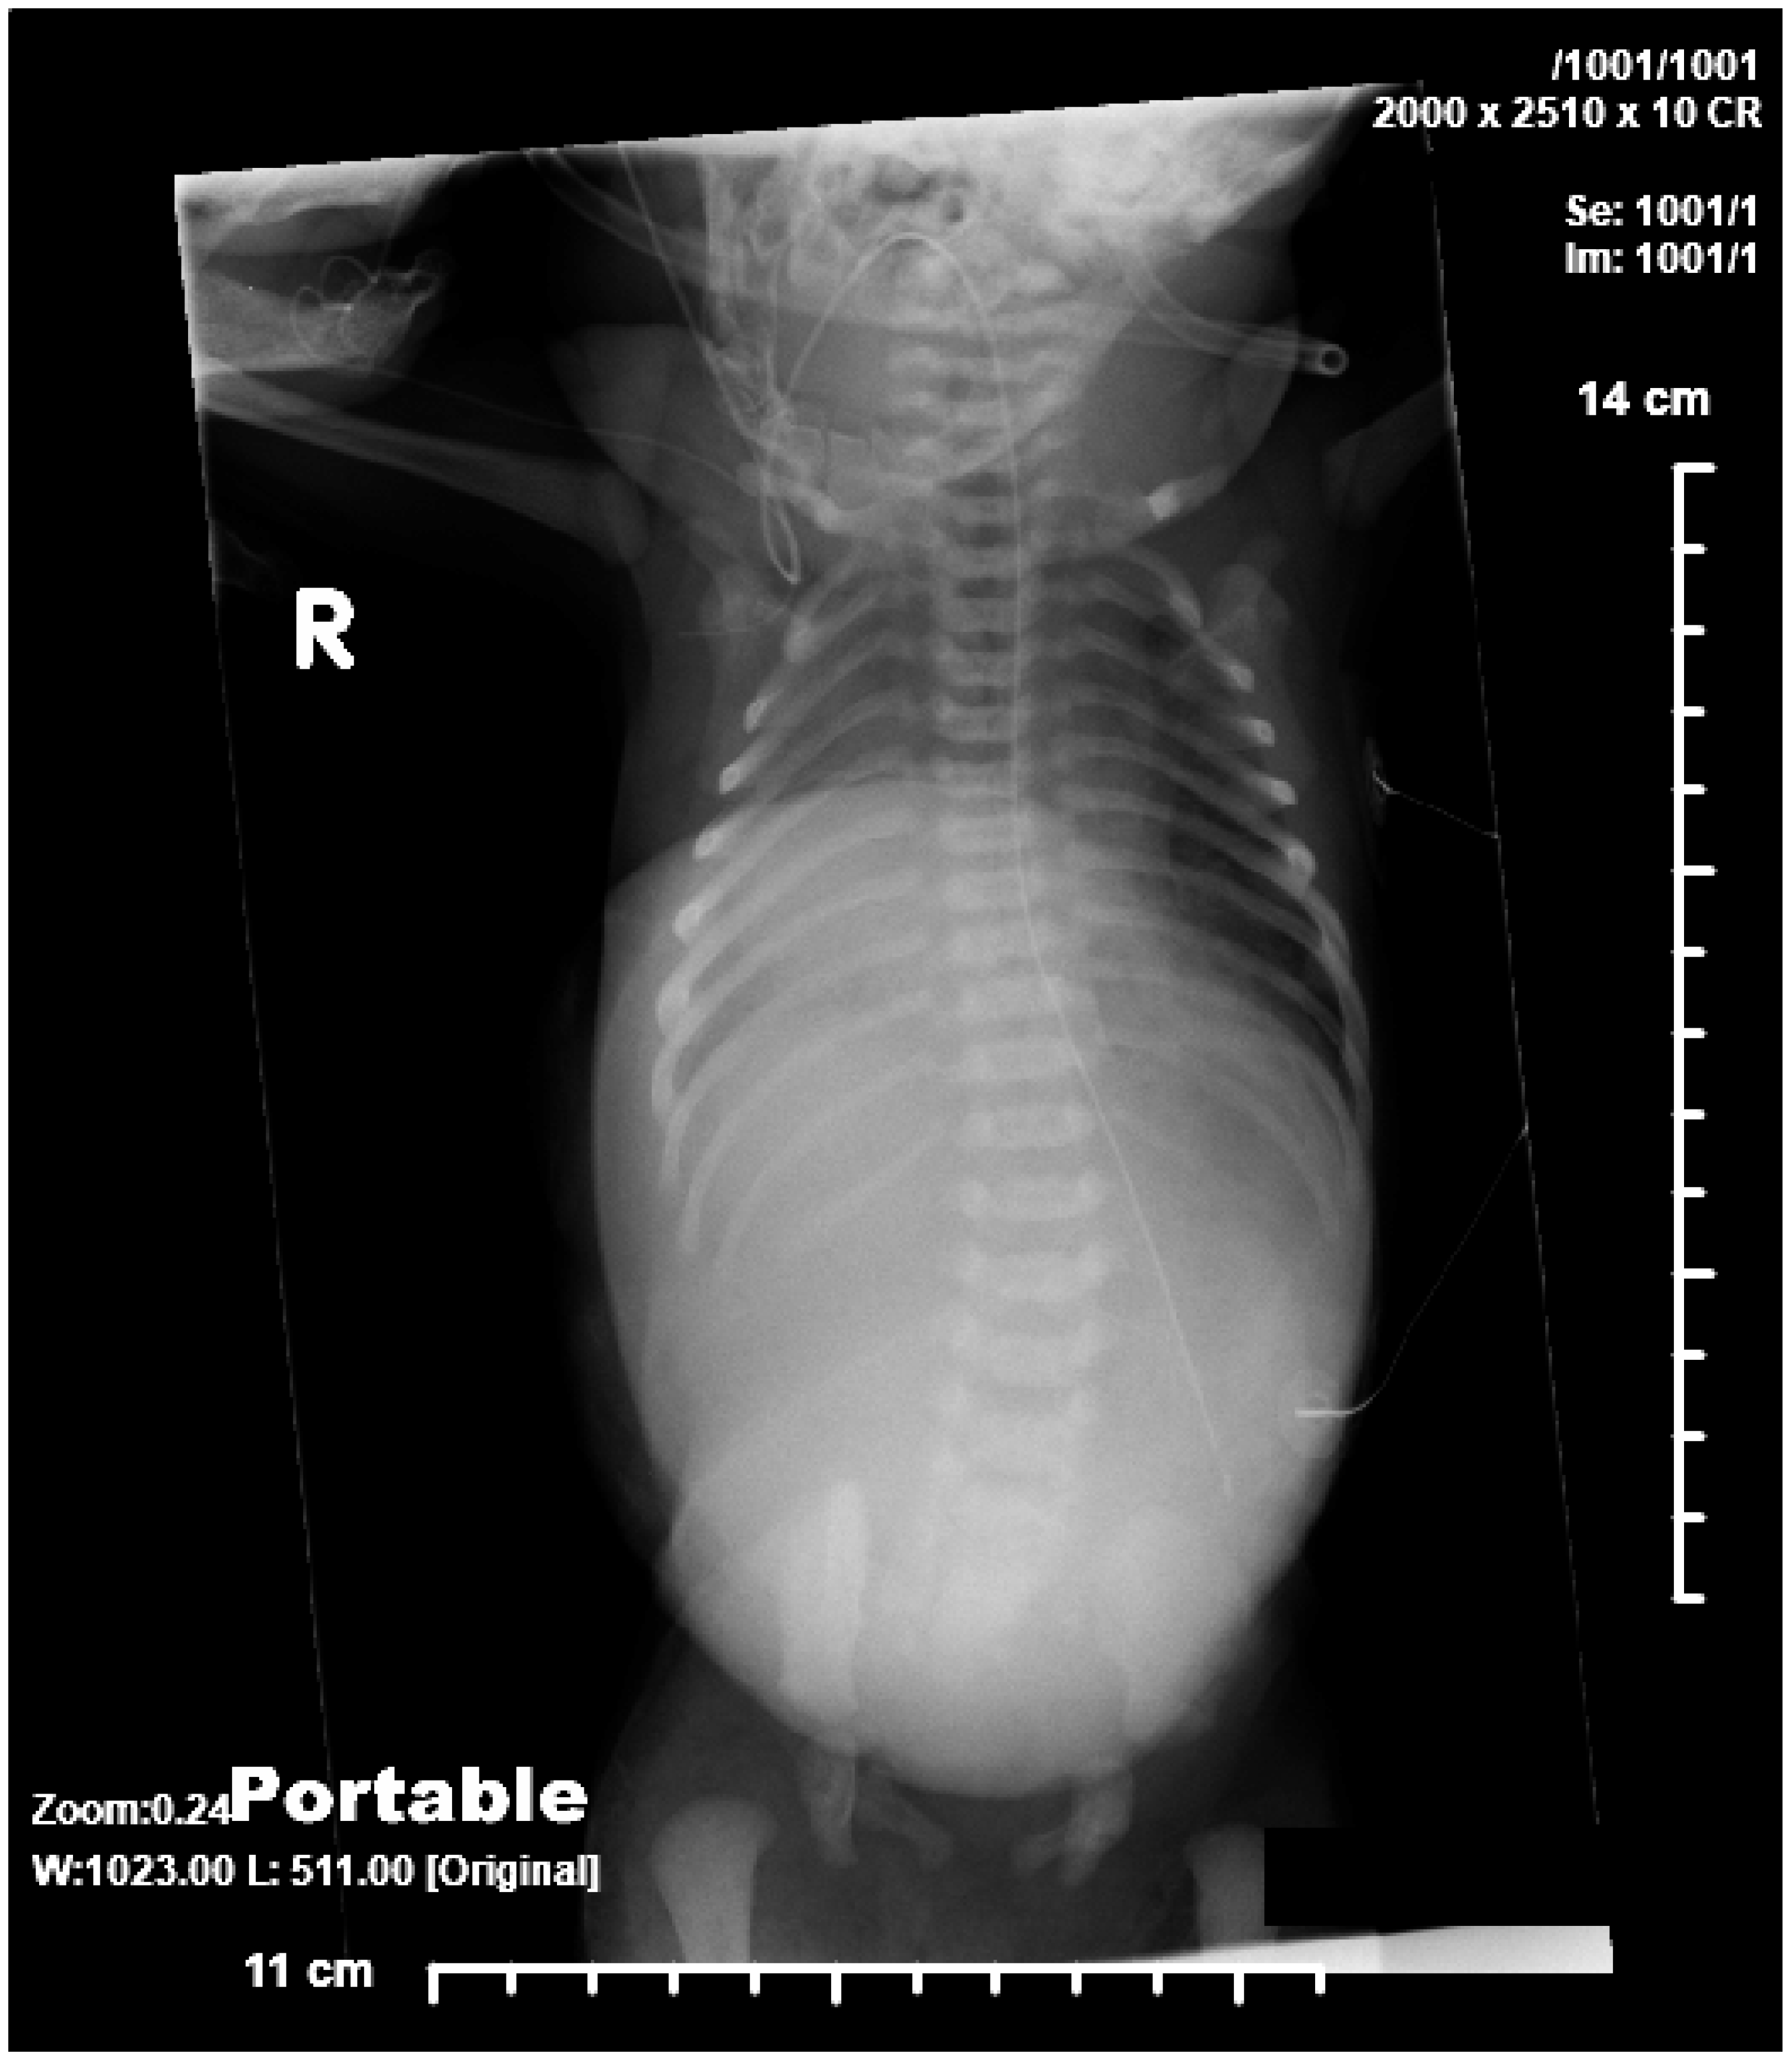

2.1. Case 1